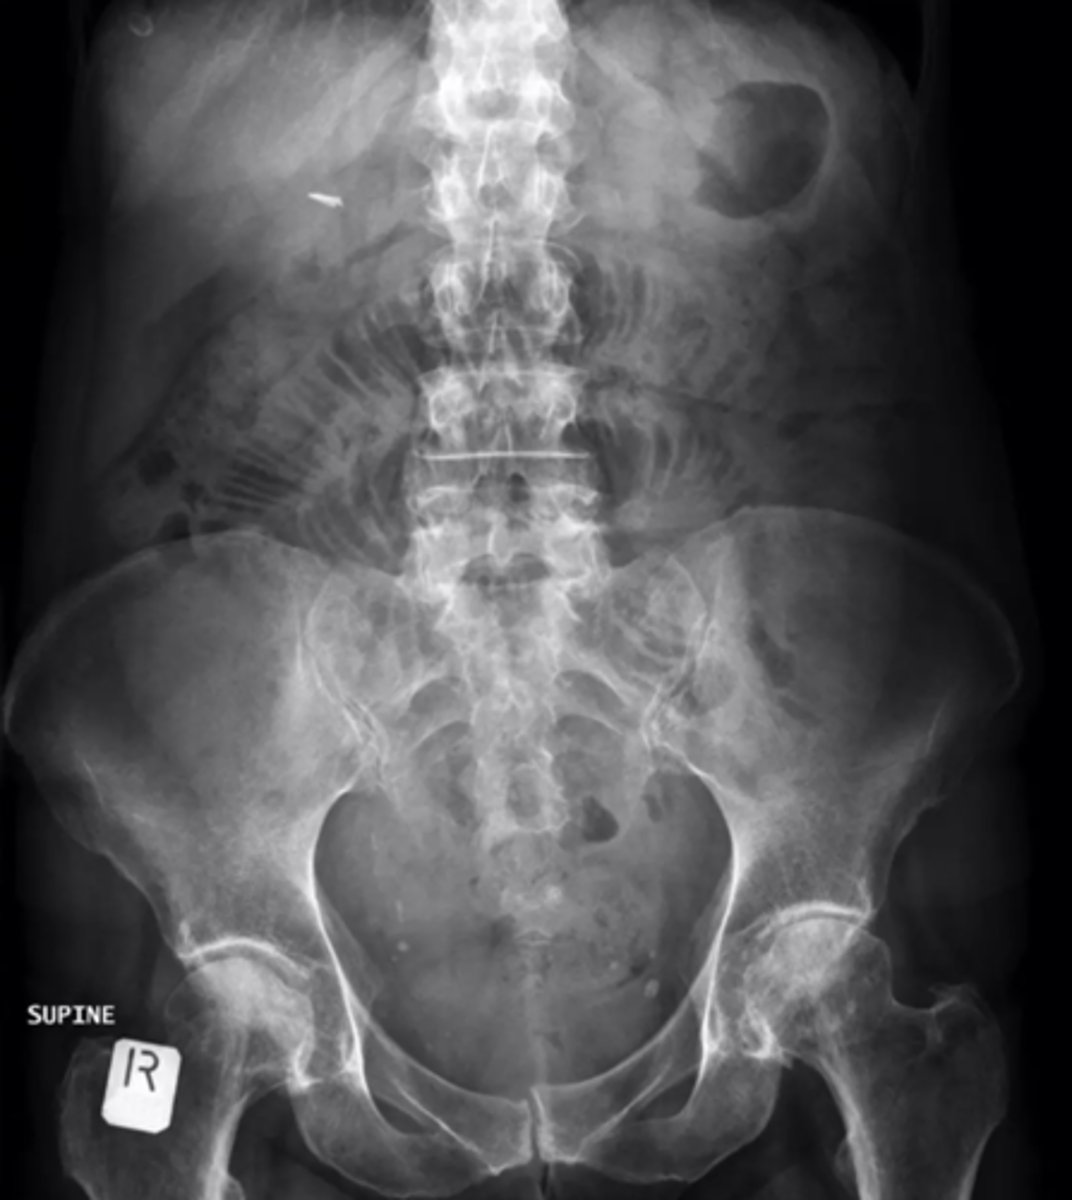

dilated loops of bowel air fluid levels

dilated loops of bowel

small bowel obstruction usually starts in the ______

LUQ

causes of SBO

post-operative adhesions, malignancy, hernias, gallstone ileus, intussusception, IBD

string of pearls sign- diagnostic of mechanical obstruction

stretch sign- small pockets of gas trapped bn valvulae conniventes within fluid filled bowel